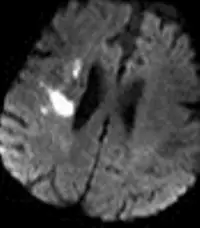

- 影像序列與特徵:此為一張腦部的軸狀切面(Axial view)磁振造影(MRI)。影像中腦脊髓液(CSF)呈現暗訊號,且病灶呈現極端明亮的高訊號(Hyperintensity),這種對比度特徵典型屬於擴散加權影像(Diffusion-Weighted Imaging, DWI)。

- 病理意義:在 DWI 影像上出現明顯的高訊號,代表該區域的水分子擴散受限(Restricted diffusion),臨床上最常見的原因為急性缺血性腦中風(Acute ischemic stroke,即急性腦梗塞)。

- 解剖位置:觀察影像,高訊號病灶位於大腦右側(影像左側即為病患右側)的側腦室(Lateral ventricle)外側,涵蓋了額頂葉的深部白質(放射冠 Corona radiata / 半卵圓中心 Centrum semiovale)以及部分鄰近皮質下區域。